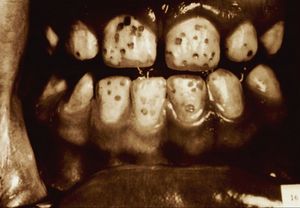

경미한 반상치의 경우, 치아 법랑질 표면은 대체로 손상되지 않고 단단하며 매끄럽지만, 경계가 불분명한 불투명한 흰색 반점이나 주름선(perikymata)을 따라 좁은 흰색 선이 나타나는 특징을 보인다.[7] 상태가 심해질수록 치아 표면 아래의 법랑질은 더욱 다공성(구멍이 많아지는 상태)이 된다. 이로 인해 법랑질은 황색이나 갈색으로 변색되거나, 충치와 유사하게 움푹 들어간 흰색-갈색 병변이 여러 개 나타날 수 있다. 이러한 외형은 흔히 "얼룩덜룩한 치아"라고 묘사된다.[8]

반상치 자체가 직접적으로 치아 변색을 일으키는 것은 아니다. 반상치의 영향을 받은 영구치가 처음 입안으로 나올 때는 아직 변색되지 않은 상태이다. 반상치는 법랑질 표면 아래에 미세한 구멍(다공성)을 만들거나 저석회화를 유발하는데, 상태가 진행되면 이러한 변화가 상아질-법랑질 경계면까지 확장된다. 이렇게 다공성이 증가한 법랑질은 외부 물질에 의한 착색에 더 취약해진다. 시간이 지나면서 음식물이나 음료 등에 포함된 외인성 이온(예: 철, 구리 이온)이 비정상적으로 다공성이 된 법랑질에 침투하여 점차 얼룩을 만들게 된다.[7]

반상치는 치아가 발달하는 시기에 불소를 과다 섭취하여 법랑질 형성에 이상이 생기는 질환이다.[13] 과도한 불소는 법랑질의 정상적인 광화 과정을 방해하여 표면 아래가 저석회화되고 다공성 구조를 띄게 만든다.[7] 이로 인해 치아 표면에 흰색 반점이나 줄무늬가 나타나며, 심한 경우 황갈색으로 변색되거나 표면이 패일 수 있다.[7][8] 이러한 변화는 주로 영구치에 나타나며, 시간이 지남에 따라 외부 물질에 의해 착색될 수 있다.[7]

과거에는 심한 불소증을 에나멜 형성 부전의 한 형태로 설명하기도 했으나, 실제로는 형성 부전 자체가 불소증의 결과로 발생하는 것은 아니다.[32] 심한 불소증에서 관찰되는 에나멜의 구멍, 줄무늬, 손실 등은 치아가 입안으로 나온 후, 심하게 석회화가 저하되고 부서지기 쉬운 에나멜이 손상되어 나타나는 결과이다.[32]